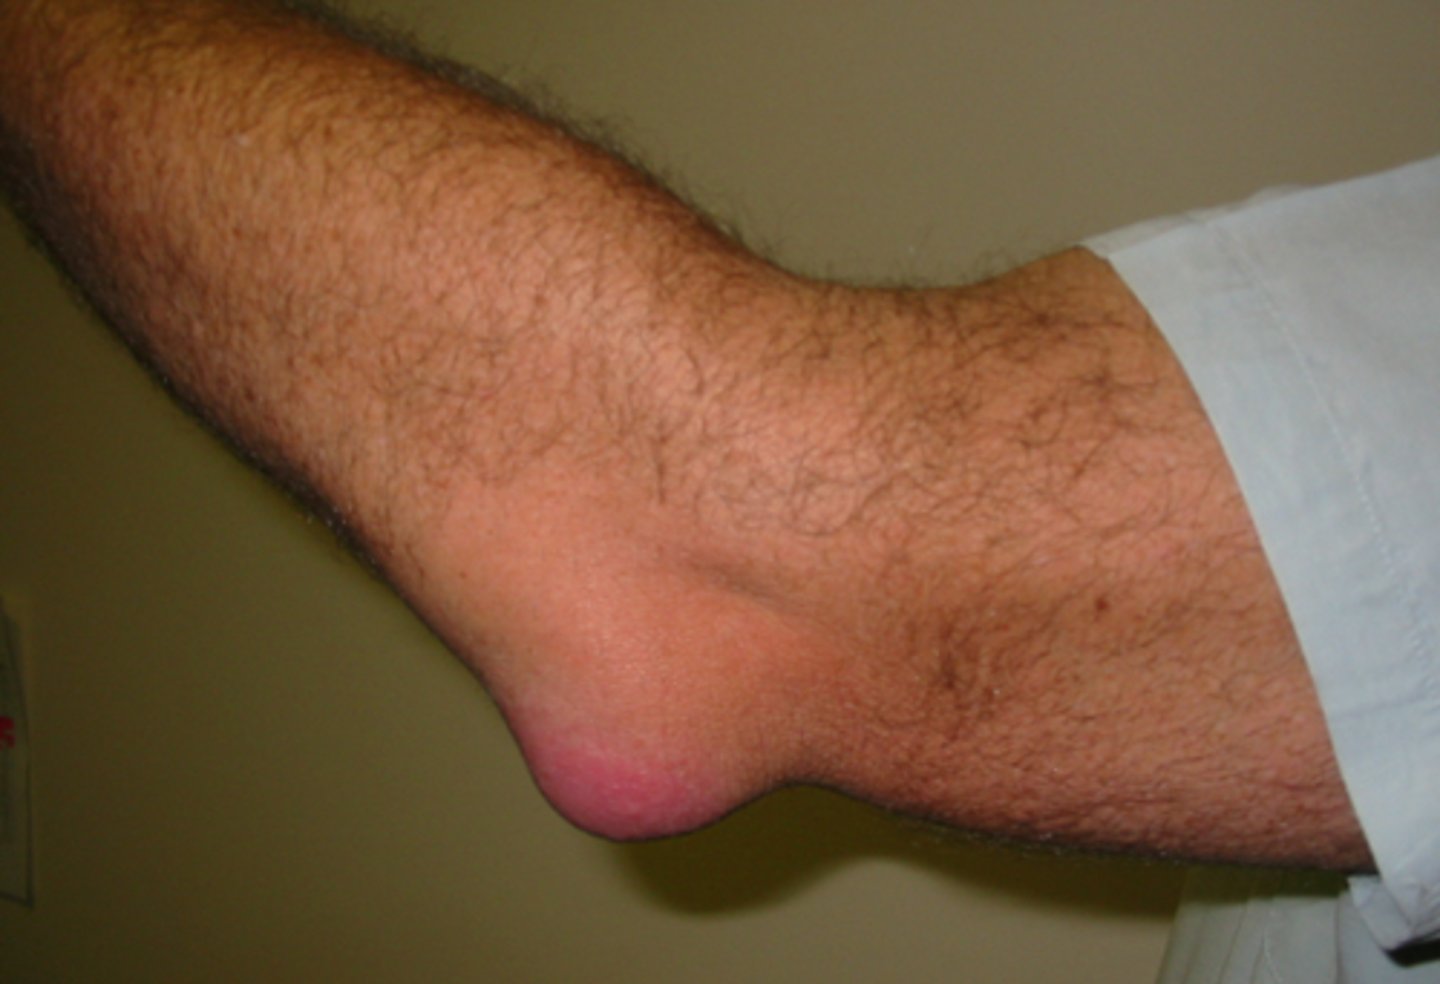

olecranon bursitis

-student's elbow, elbow bursitis

-swelling over posterior elbow